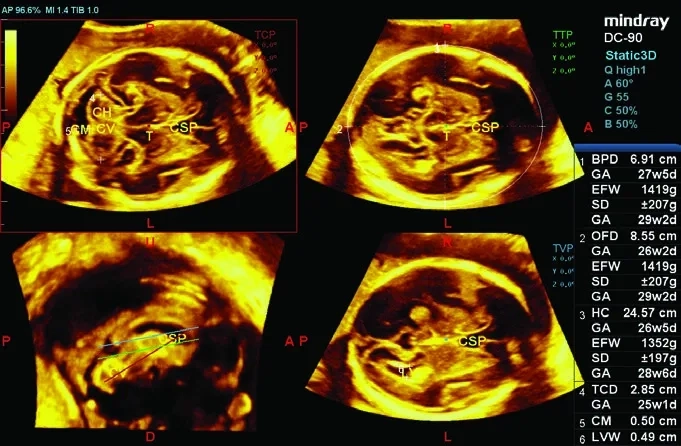

• Smart 3D — ПО для построения 3D-изображений с использованием 2D-датчиков;